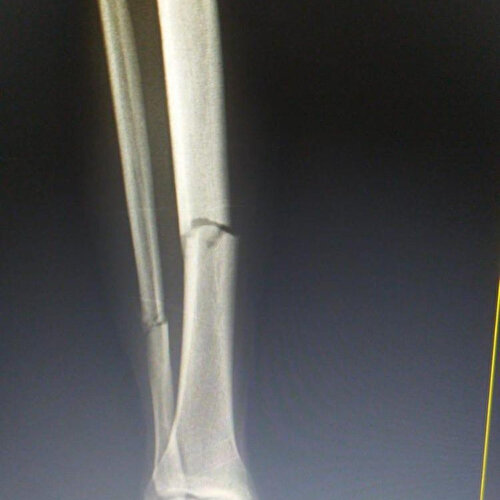

Muslera'nın hastanede yapılan kontrollerinde sağ ayak tibia ve fibula kemiklerinde kırık tespit edildi. Çekilen röntgen sonrası Uruguaylı kalecide 2 kırık tespit edilirken, intrameduller çivi takılarak sağlığına kavuşturulacağı öğrenildi. Muslera'nın sahalardan en az 6 ay uzak kalacağı tahmin ediliyor.